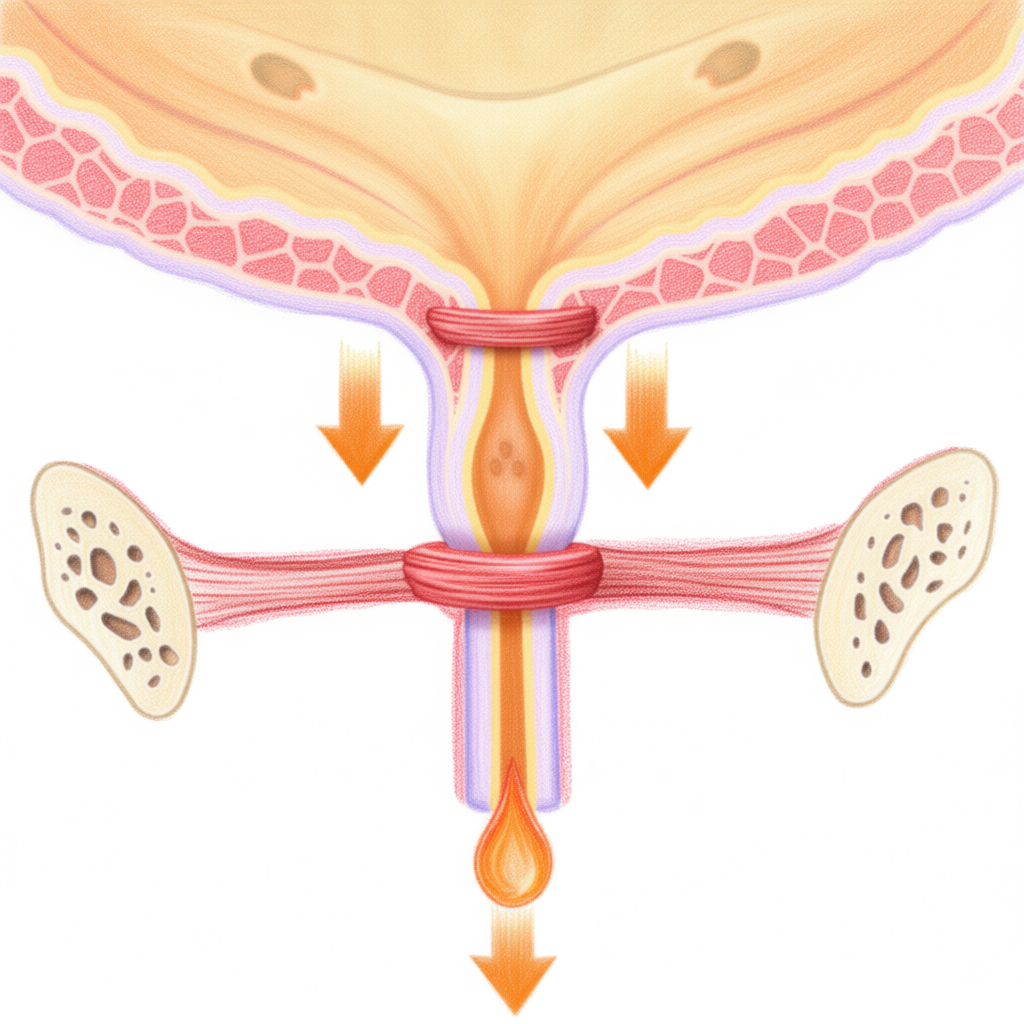

PRED:

Oslabené svaly močovej rúry

PO:

Posilnené svaly močovej rúry